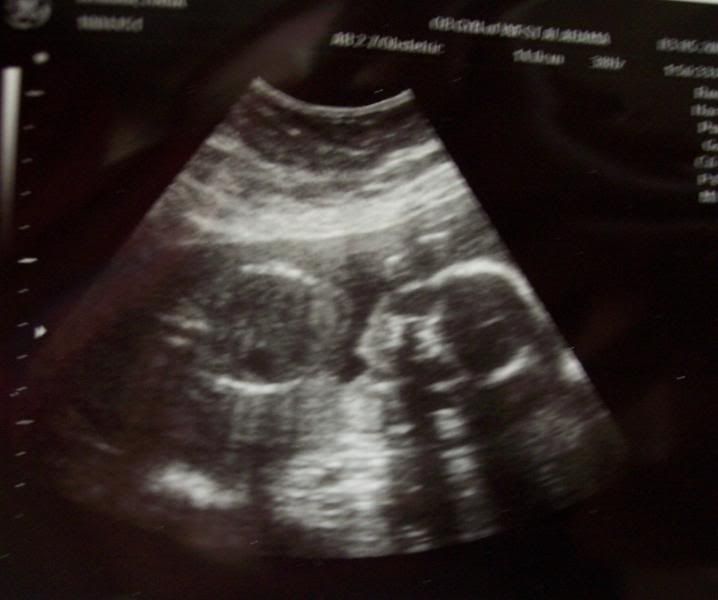

Hey, mama!